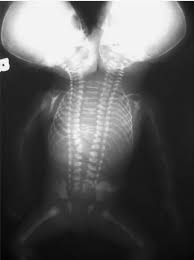

医生发现,她们属于典型的双头连体双胞胎(Dicephalic parapagus twins)。

这对姐妹有着两个头,两条脊柱、脊髓,在尾骨交汇。

4 个肺,2 个胃、2 胆囊,消化道以 Y 形在小肠合并。

3 个肾,2 左,1 右。

2 颗心脏共享血液循环系统。

其它的身体结构和四肢基本上就是一套了,阿比盖尔控制右侧肢体,布列塔妮控制左侧肢体。